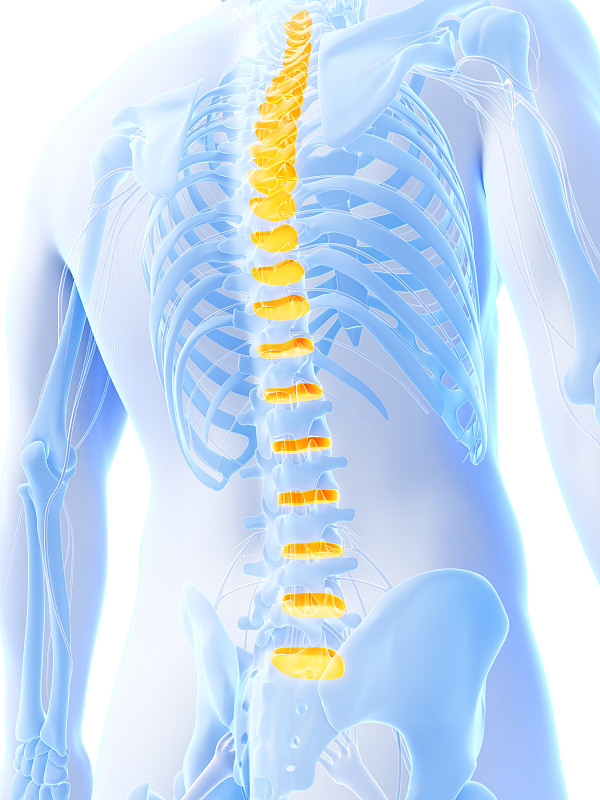

腰椎解剖在蓝色细节详情

JPG